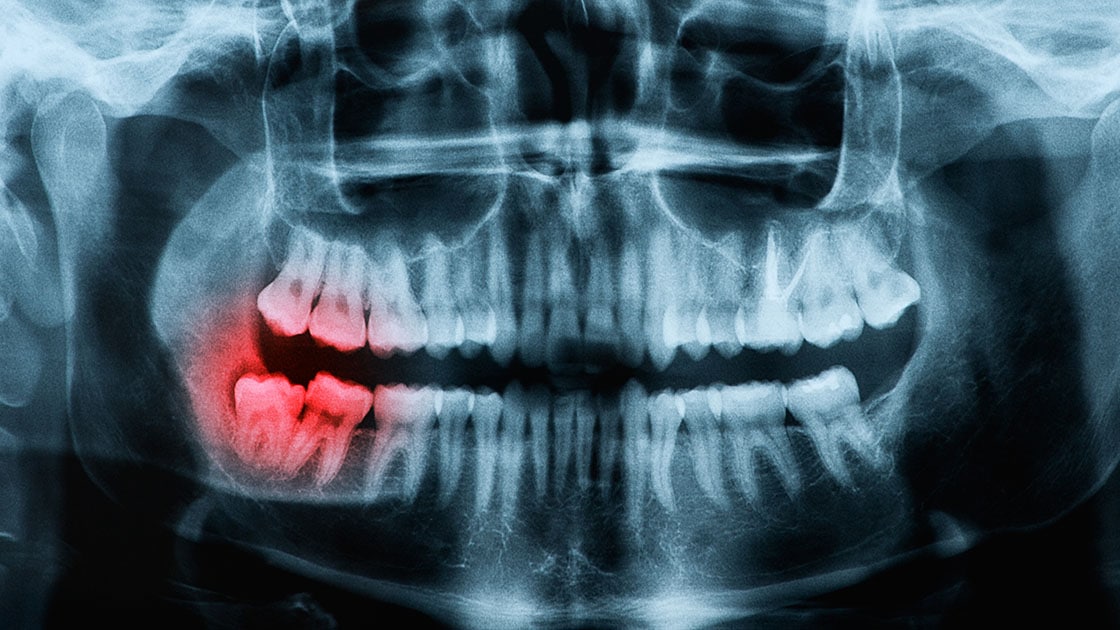

Wisdom Teeth

Wisdom Tooth Removal (3rd Molars)

A wisdom tooth that is deemed problematic is normally extracted to avoid any oral complications. To have a wisdom tooth removed, a small incision is made to open up the gum tissue over the tooth and remove any bone that is covering the tooth. Once the tooth is in view, it is grasped with a dental instrument, known as a forcep, and gently rocked back and forth to loosen it from the jaw bone and surrounding ligaments. Sometimes the tooth may need to be cut into smaller pieces to make it easier for removal. Stitches may be necessary after the removal of a wisdom tooth.